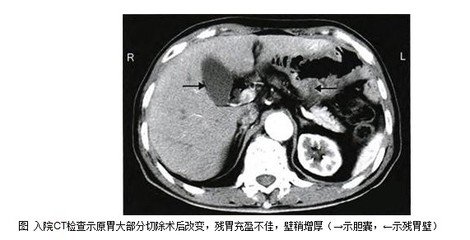

胃大部切除术后6种并发症及饮食营养治疗